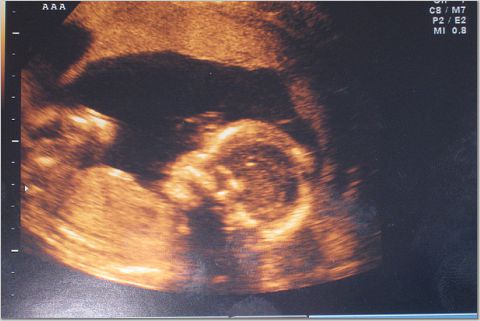

I just wanted to write a quick note and let everyone know that we went for our 20 week (5 month) sonogram this morning.

Most importantly, everything is moving along very nicely. Both twins are growing on schedule, all the organs are in place, and there are no signs of any problems.

I have attached a few sonogram photos. The third picture is our favorite, as you can see both heads in the same shot.